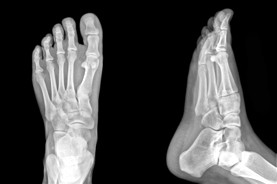

The Foot Institute is an association of Grande Prairie Doctors specializing in the medical treatment of the foot and ankle, and is one of the largest groups of foot specialists in Alberta.

The Grande Prairie Foot Institute is dedicated to the medical and surgical treatment of the foot. Our mandate is to provide the best possible medical, surgical and preventative treatment available for our patients. We do this by providing well-trained Doctors who are committed to treat and prevent all types of foot pain, biomechanical disorders, as well as all other problems relating to the feet.

At the Grande Prairie Foot Institute, our Doctors are trained to specifically treat problems associated with your feet or ankles. Below are several of the most common problems that we see on a day to day basis: